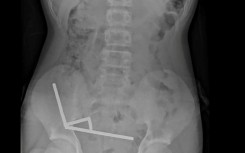

This undated handout released on October 24, 2025 from the New Zealand Medical Journal (NZMJ) shows an x-ray image of pieces of high-power magnets clumped up in the intestines of a New Zealand teenager in Tauranga

Surgeons remove up to 100 magnets from New Zealand teen's gut